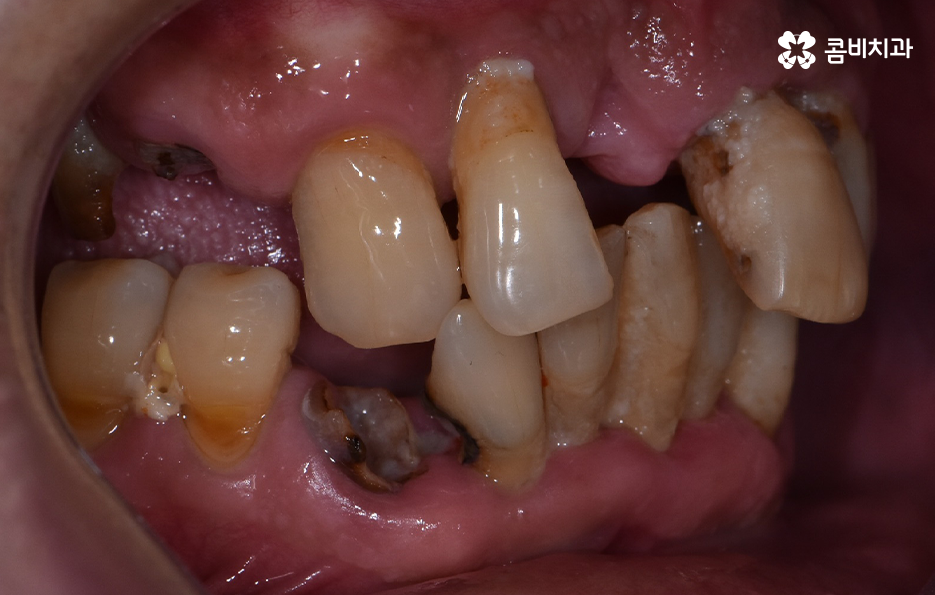

치주염으로 인해 잇몸이 내려앉고 치아의 뿌리가 흔들려서 발치했어요

위 환자분의 엑스레이 사진을 보면 치아의 뿌리 부분에 가깝게 잇몸이 내려앉은 것을 볼 수 있는데 치아의 구조에서 뿌리쪽은 법랑질이 없기 때문에 잇몸이 내려앉고 잇몸 뼈가 치주염으로 녹게 되면 치아가 너무 아파서 식사를 하기에도 어렵고 물 한잔만 마셔도 이가 시릴 정도로 일상에 지장을 느끼실 수 있어요

고령의 환자분들의 경우에는 잇몸 뼈의 상태 뿐 아니라 전신질환, 회복력을 함께 고려해야 하기 때문에 치료 계획에 있어서 보다 섬세하게 체크해야 하며 환자분의 잇몸 뼈 상태와 전신건강 그리고 경제적인 상황 등을 고려할 때 전체임플란트를 하게 되는 경우도 있지만 위 환자분의 사례처럼 임플란트를 최소한으로 식립하여 임플란트의 보철물을 연결하여 치아의 기능을 회복하는 경우도 있는데요

치주염 발치 해야 하는 상황으로 대부분의 치아를 잃게 된 경우이거나 임플란트를 여러개 식립하기에는 경제적 부담이 크다면 임플란트의 식립 개수는 최소화하고 보철물을 틀니처럼 사용하시는 경우도 있는데요. 앞니의 경우 식사 시에 치아에 받는 압력이 어금니에 비해 적은 편이지만 어금니의 경우 충분한 저작력을 유지하기 위해서는 충분한 두께의 잇몸 뼈에 임플란트를 식립해야 하기 때문에 잇몸 건강의 중요성에 대해 꼭 늦지 않게 신경써주시길 바라고 있어요